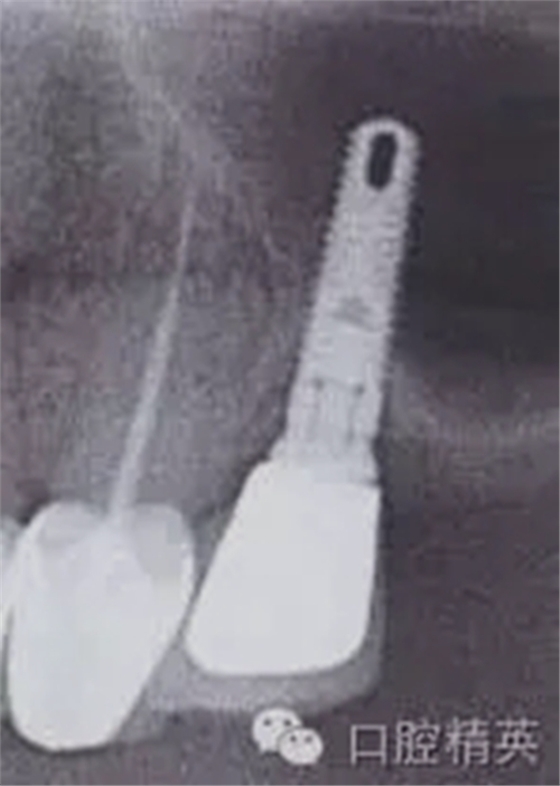

圖5b:術(shù)后對(duì)25號(hào)牙區(qū)域進(jìn)行iCAT CBCT斷層片成像診斷,其結(jié)果揭示了種植體和其周圍解剖結(jié)構(gòu)的頰舌向位置關(guān)系,顯示嚴(yán)重的頰側(cè)骨板缺如,至少三分之一的頰側(cè)螺紋暴露。

缺如,至少三分之一的頰側(cè)螺紋暴露。